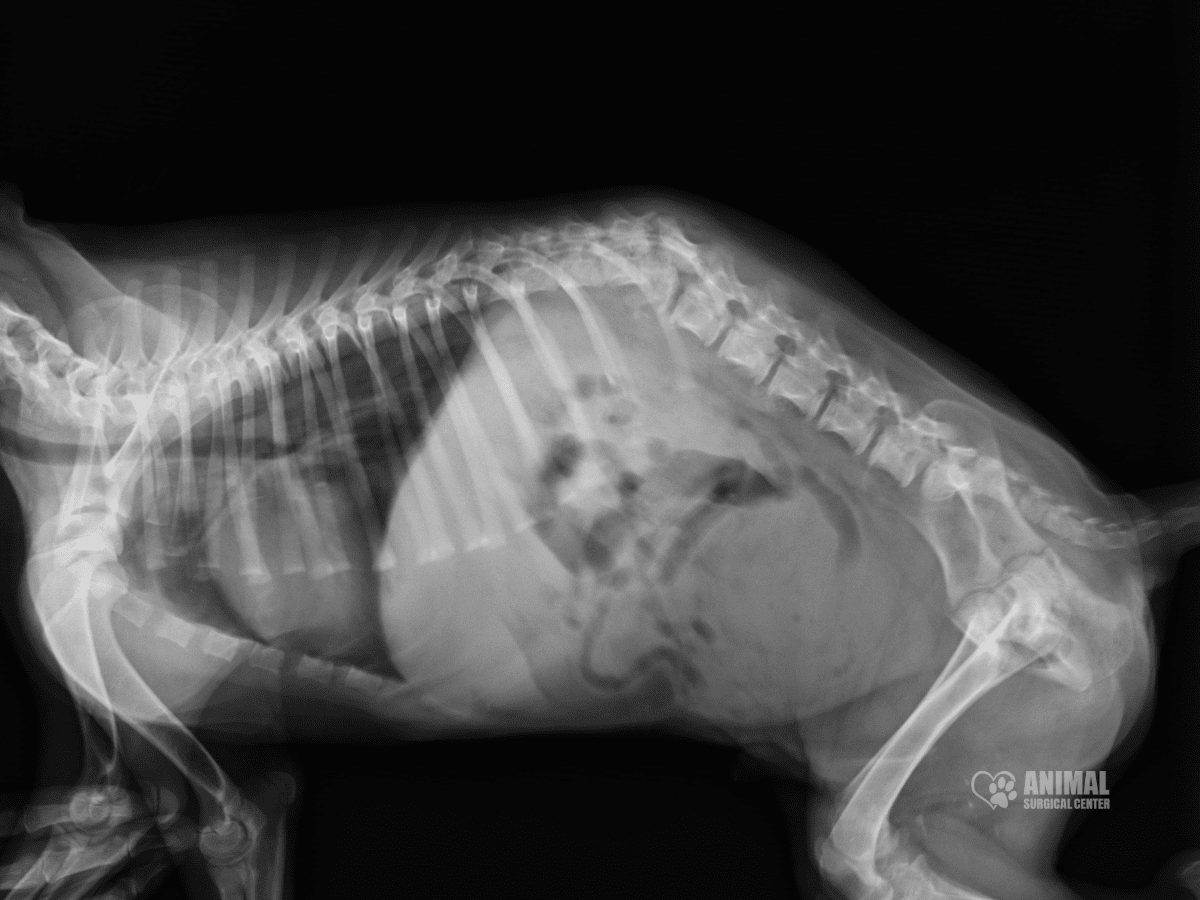

Diagnosing Spinal Issues with CT Scans

Accurate diagnosis is the first critical step in treating spinal issues. At the Animal Surgical Center, we rely on advanced imaging technologies, such as Computed Tomography (CT) scans and myelograms, to gain a detailed view of your pet’s spine. Unlike standard X-rays, CT scans provide cross-sectional images that allow us to detect conditions like herniated discs, spinal tumors, fractures, and other abnormalities with exceptional clarity.

Performed under light anesthesia, CT scans are non-invasive, keeping your pet comfortable and still throughout the process. These detailed images play a key role in planning the most effective surgical approach, ensuring the best possible outcomes for each patient.